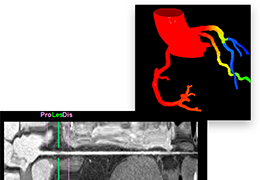

成像智能。

Eclipse 成像智能功能提供强大的处理能力和最佳质量的影像,同时减少质量错误并提高剂量效率。

凭借 AI、专有算法和先进的影像处理能力,提供出色的影像质量和无与伦比的诊断信心。

工作流智能。

在这里,先进的智能功能自动执行手动任务和工作流程步骤,以简化流程,提高技术人员工作效率,节省时间和金钱,并增强患者护理。

自动化设备定位和患者姿势确认可优化放射科技师的效率并加快工作流程。

自动技术选择可改善影像一致性并支持辐射剂量控制。